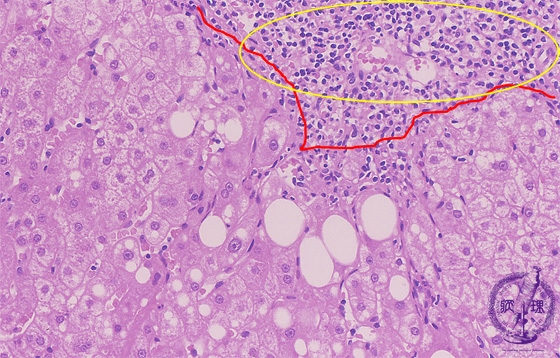

Microscopic image (HE stain, high power view): There is dense portal chronic inflammation with interface hepatitis comprising lymphocytic inflammation at the limiting plate and concurrent hepatocellular drop-out (yellow box). Hepatocytes contain large cytoplasmic lipid droplets (steatosis).